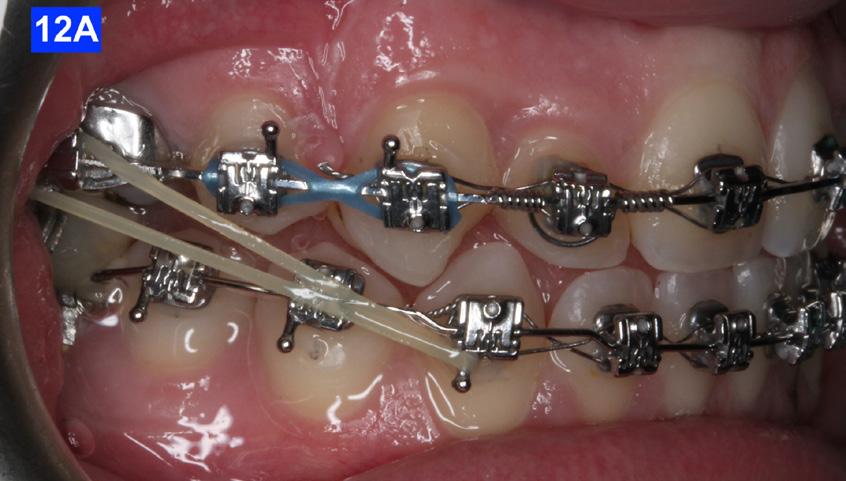

The final labial movement and de-rotation was done by the combined use of an Adrian “U” bend spring and an EC (a .016 SS and a .014 NiTi) (10 – D, E, F). When the maxillary lateral incisors settled in their proper site, the leveling of the maxillary arch was initiated. The progression of the arch wires was a .016 NiTi, a .0.18 NiTi, a .018 SS and the final arch wire, a .019 x .025 SS. There was only a .018 SS arch wire in the mandible. The remaining spaces were closed with a combination of the OCS, EC, and triangular elastics (1/4” – 4.5 oz) (Figure 11-A).

Class III inter-arch elastics (1/4” – 4.5 oz) were introduced to improve the inter-digitation (Figure 12 – A, B).

Figure 10E: Maxilla, occlusal view Figure 10F: Mandible, occlusal view Figure 11A: Frontal view Figure 12A: Class III elastic, right lateral view Figure 12B: Class III elastic, left lateral view Figure 11B: Goodman torquing spring Figure 11C: Goodman torquing spring in situ